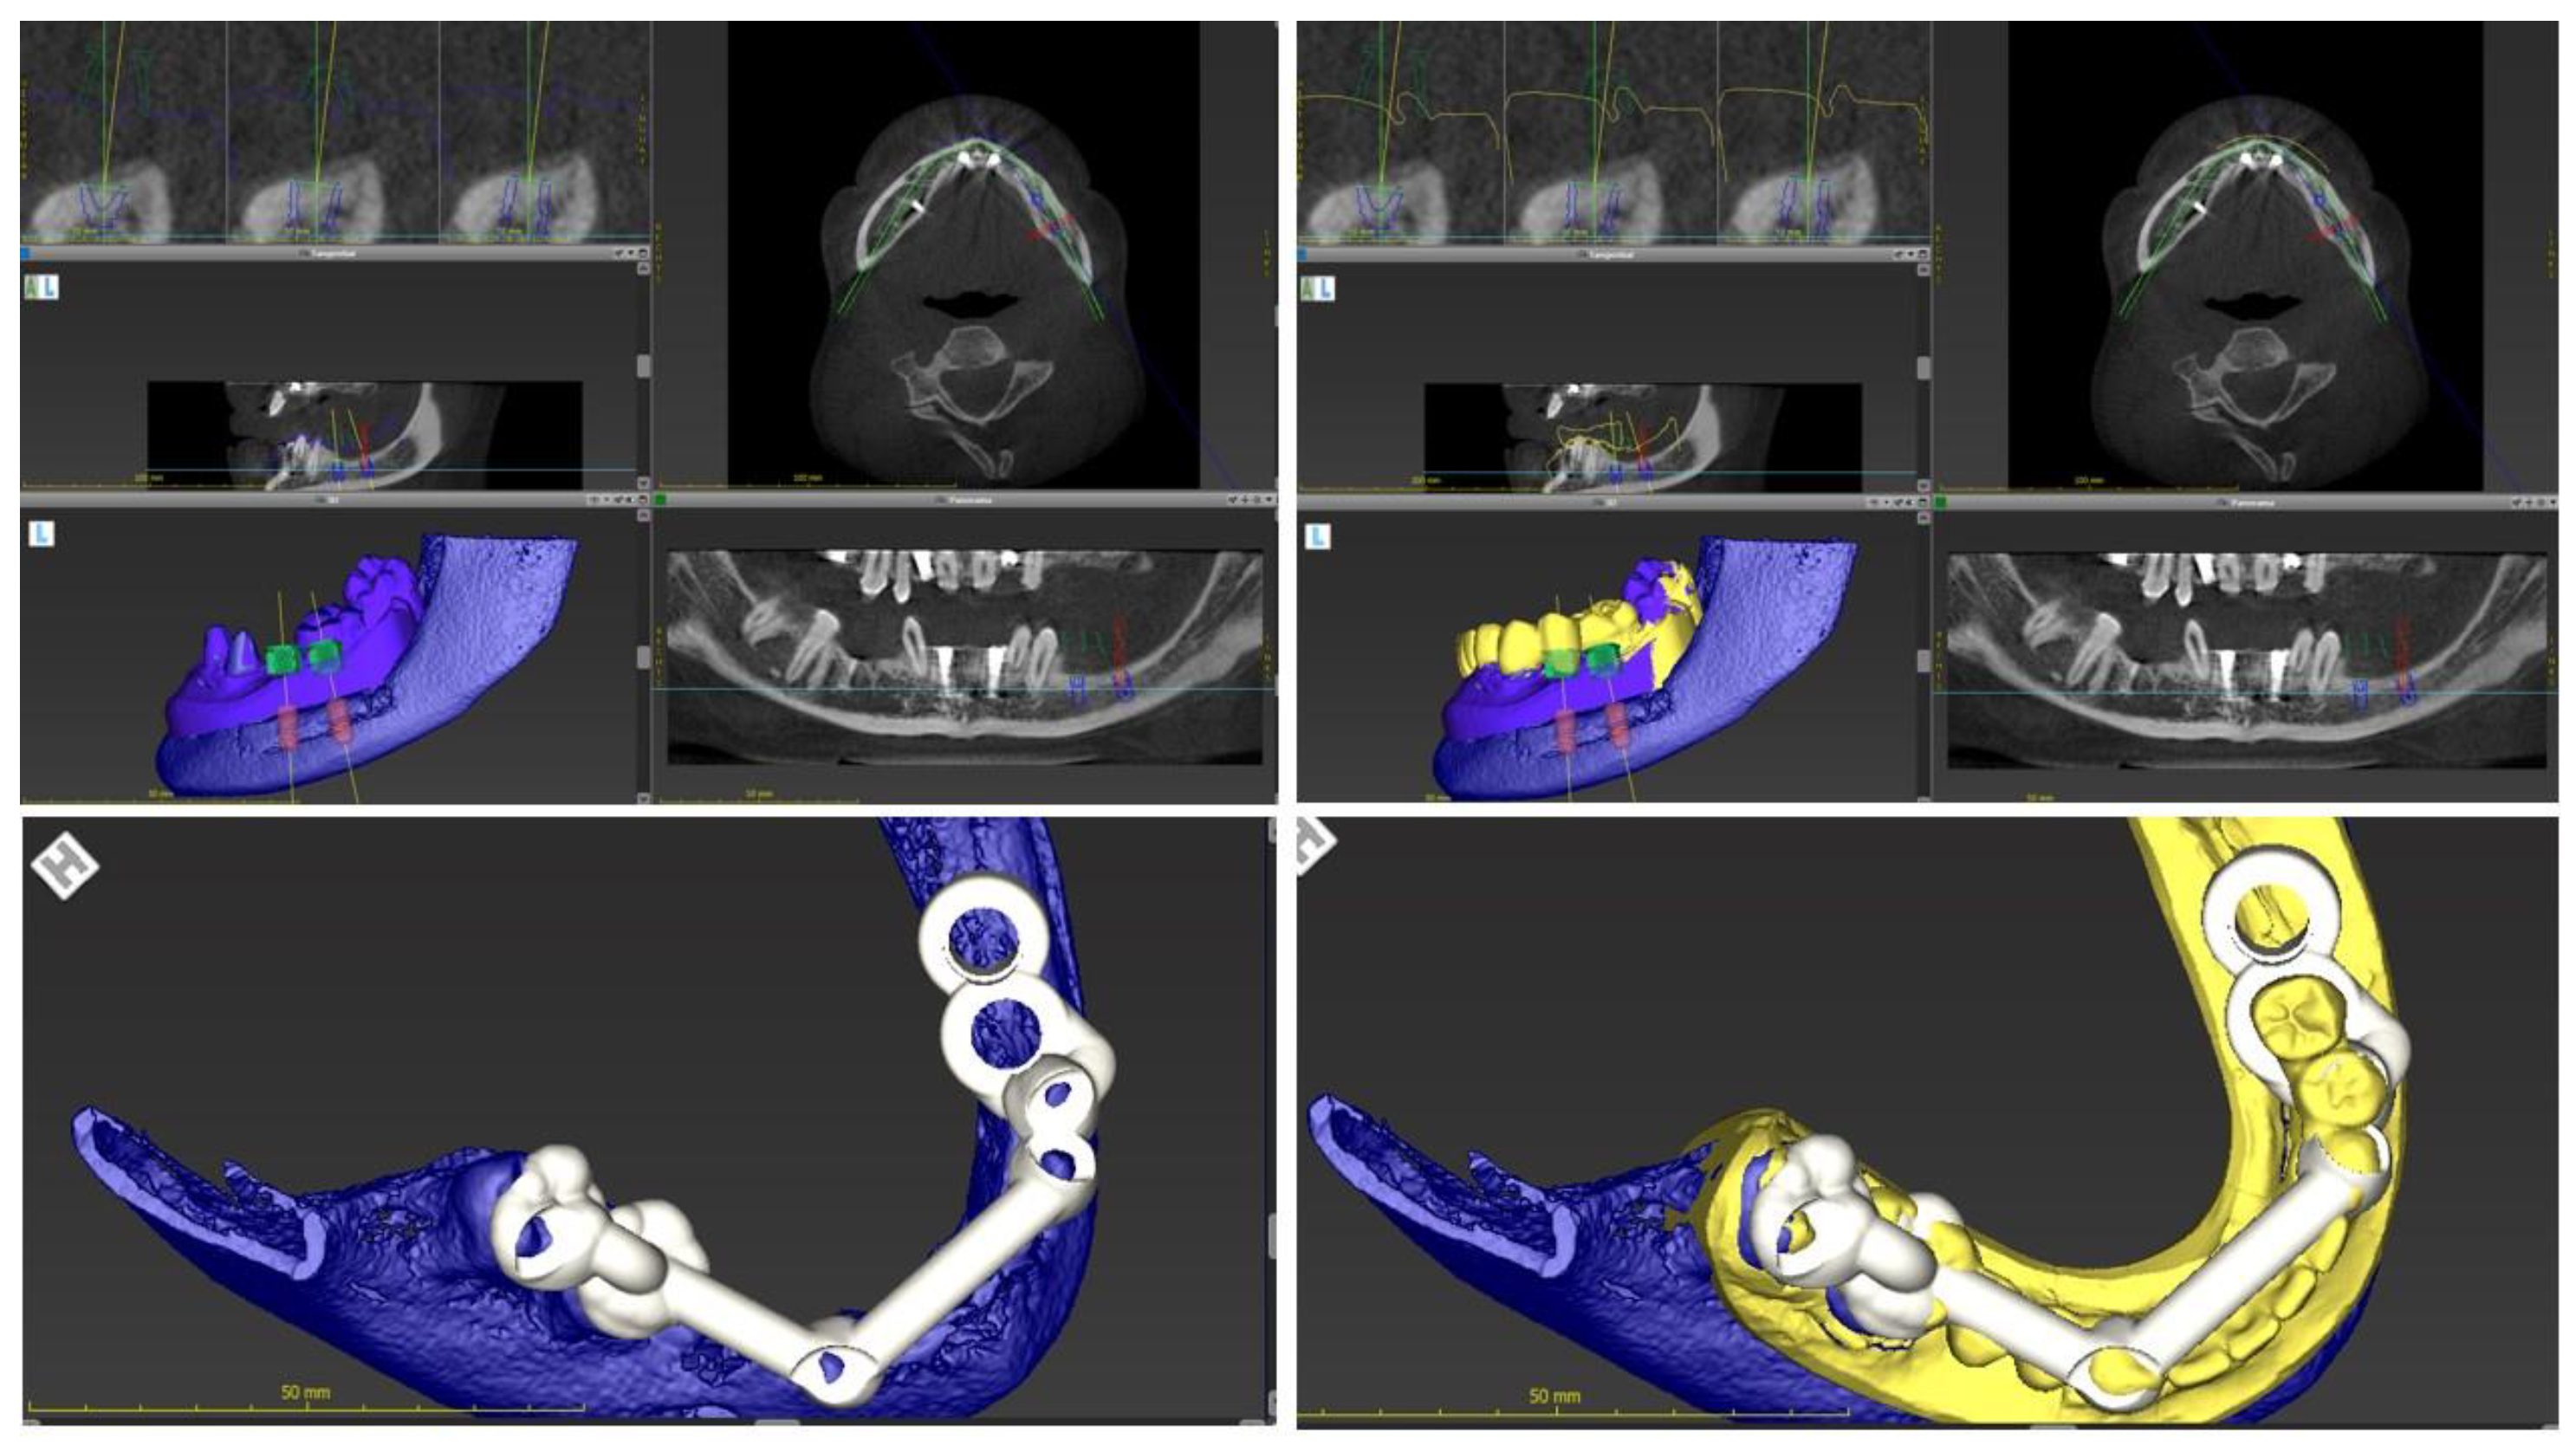

2.1. Case One